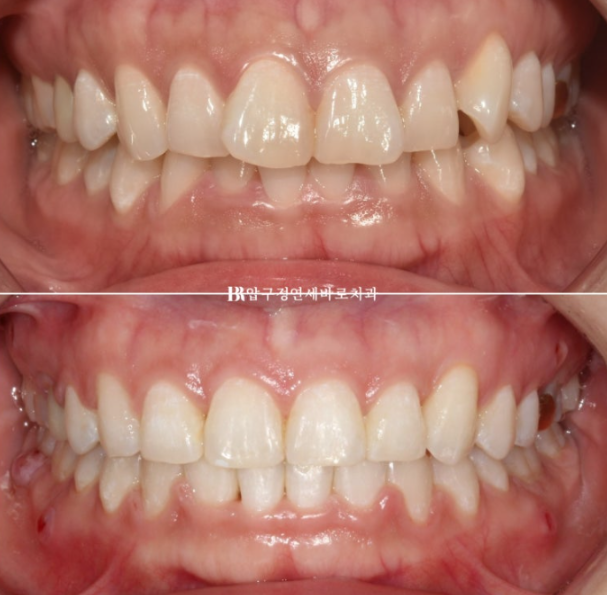

23.04~24.10

잇몸 노출량이 줄면서 잇몸미소 거미스마일 많이 좋아졌죠?

소량의 입동굴이 생겼고 과하지 않은 입동굴은 여성스러운 미소 심미를 개선시킵니다.

돌출되지도 옥니처럼 쓰러지지도 않는 일자로 딱 떨어지는 적절한 앞니 각도 개선된 잇몸 노출량

비포 애프터 사진을 보면 환자분들은 그제서야 내가 잇몸이 원래 많이 보였구나 하고 감탄하십니다.

잇몸미소 거미스마일 교정은 치료 후 미소의 완성도를 200% 끌여주죠

단순 배열이나 돌출개선을 넘어서 좀 더 완성도 있는 결과를 위해 최선을 다합니다.